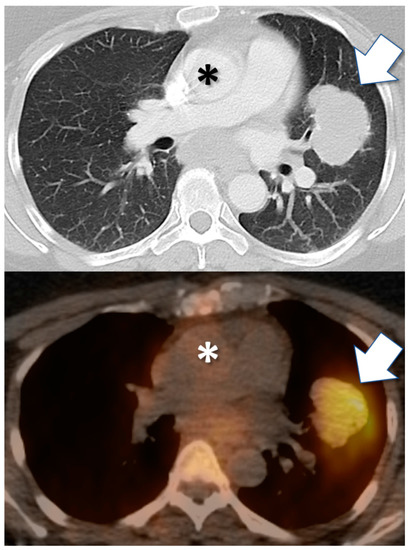

- Krebs, S.; Veach, D.R.; Carter, L.M.; Grkovski, M.; Fornier, M.; Mauro, M.J.; Voss, M.H.; Danila, D.C.; Burnazi, E.; Null, M.; et al. First-in-Human Trial of Dasatinib-Derivative Tracer for Tumor Kinase-Targeted Positron Emission Tomography. J. Nucl. Med. 2020. [Google Scholar] [CrossRef]